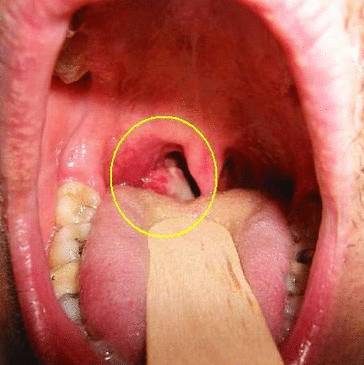

Опухоль в горле – фото:

Для определения типа онкологического поражения специалист назначает проведение дополнительных диагностических процедур: